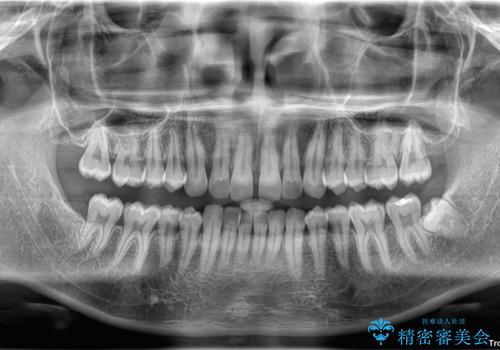

目立たない矯正で正中離開と下の前歯のデコボコを改善|インビザラインによる治療症例

- 上の前歯の正中離開(すきっ歯)と、下顎前歯部の叢生(デコボコ)を主訴に来院された患者様の症例です。

正中離開は舌の癖(舌突出癖)がある場合、後戻りしやすい傾向があります。

そのため当院では矯正治療と並行して、正しい舌の位置・飲み込み方・呼吸の仕方などをトレーニングする

**MFT(口腔筋機能療法)**を実施し、治療後の安定性を高めています。